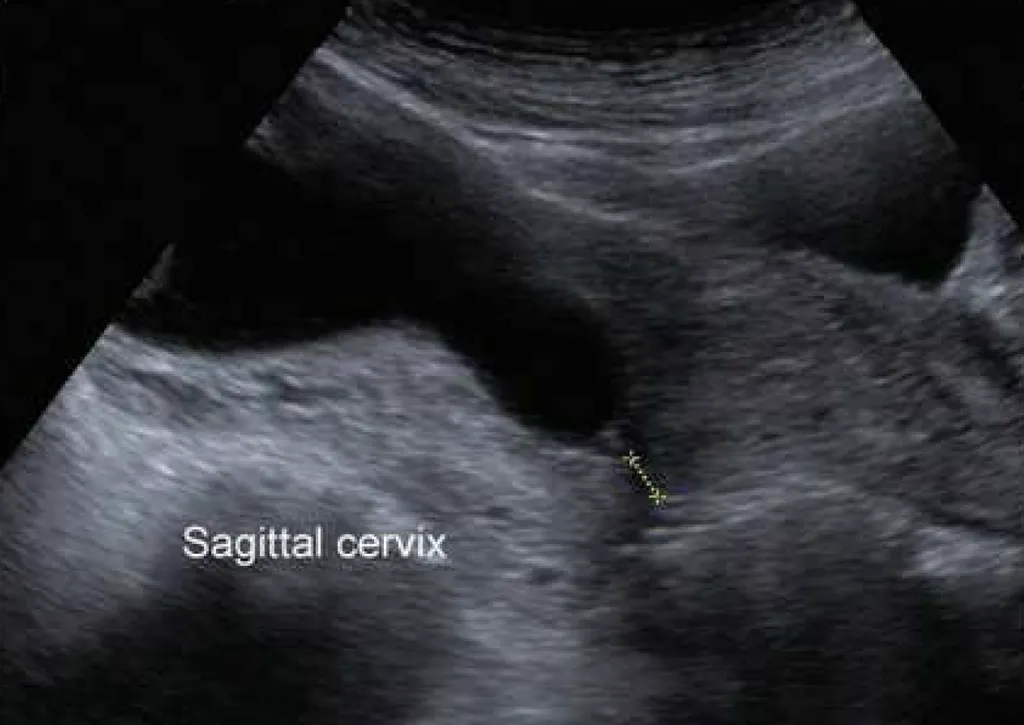

【113-1 醫學(六) 第35題】一位 31 歲懷孕 22 週 G2P1 的孕婦,來產檢時超音波檢查發現如附圖。她前一胎於懷孕 33 週時自發性早產 (spontaneous preterm),依她目前的狀況,下列何者是最適合的處置?

詳解

破題關鍵

這位孕婦有早產病史,且超音波顯示子宮頸明顯縮短並有漏斗狀變化,這代表子宮頸閉鎖不全,最適合的處置是子宮頸環紮術。

選項拆解